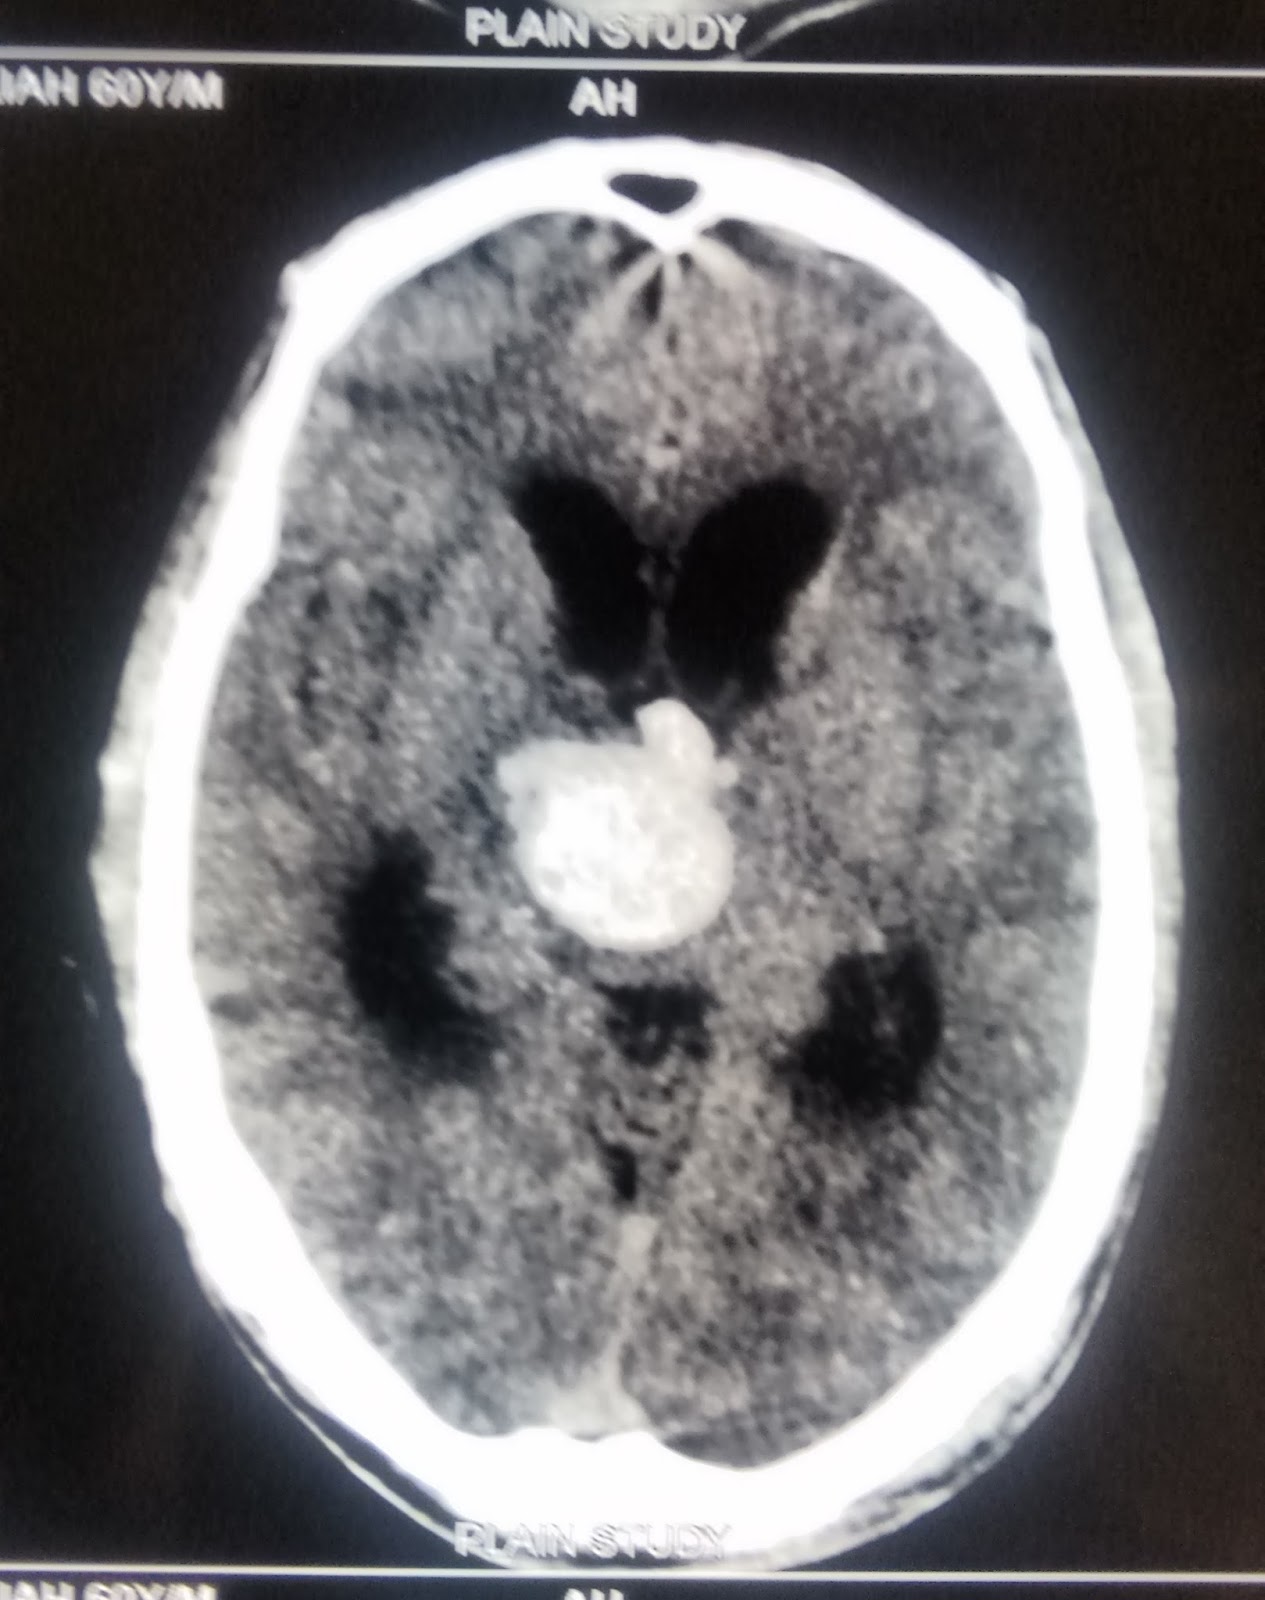

CT image of thalamic hemorrhage. Download Scientific Diagram

CT brain show left thalamic hemorrhage (Hemorrhagic stroke Stock Thalamic Hemorrhage Prognosis Recent advances in the field of radiology yielded accurate diagnoses and enabled the analysis of clinical characteristics and pathology without autopsy study. The prognosis is worse in global and medial group hemorrhages, especially those which rupture to the ventricle, than the other groups. At present, a large number of thalamic hemorrhage cases are treated with craniotomy or other surgical treatments,. Thalamic Hemorrhage Prognosis.

Plain axial CT scan, showed left thalamic hemorrhage wi Openi Thalamic Hemorrhage Prognosis The long‐term prognosis of isolated thalamic stroke is relatively favorable, with motor function being the main problem in patients with disability. At present, a large number of thalamic hemorrhage cases are treated with craniotomy or other surgical treatments, and. Recent advances in the field of radiology yielded accurate diagnoses and enabled the analysis of clinical characteristics and pathology without autopsy. Thalamic Hemorrhage Prognosis.